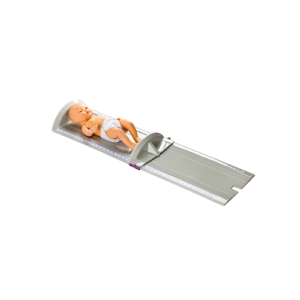

Hiflex Kids nasal cannula delivers precisely controlled, heated, and humidified air–oxygen mixtures at high flow rates to support spontaneous breathing.

Maxflow Kids nasal cannula delivers precisely controlled, heated, and humidified air–oxygen mixtures at high flow rates to support spontaneous breathing during high flow oxygen therapy.